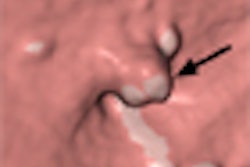

The human colon has many haustral folds, which complicate interpretation of the long, convoluted anatomy with virtual as well as optical colonoscopy. As a result, radiologists reading VC data must frequently change the viewing angle to examine the colon in 3D endoscopic views -- and still risk missing polyps and cancers that are hidden in the folds.

CAD schemes are similarly confounded by haustral folds. Current automated methods that detect polyps based on convex shapes are often fooled by the ridgelike structures lining the colon wall, leading to false-positive detections of polyps that turn out to be haustral folds. At the same time, true polyps located on or near the folds are easily missed by CAD algorithms and radiologists alike.

If haustral fold detection and analysis could be performed before polyp detection, say researchers from Japan, it would be much easier to determine if a particular feature in the CT data were a polyp or a fold, a polyp on a fold, or a plain old polyp. And it might be easier to find flat polyps, which alter the colonic mucosa in subtle ways that aren't always visible to the naked eye or to typical CAD algorithms.

"Previous CAD methods detected convex-shaped parts of the colon, so flat-shaped polyps are missed," said principal investigator Masahiro Oda from the Graduate School of Information Science at Nagoya University in Nagoya, Japan. "Because the thickness of haustral folds increases when flat-shaped polyps are located on them," flat-polyp detection could be improved by first detecting polyp folds to reveal any abnormal shapes and thicknesses, Oda said at the 2008 Computer Assisted Radiology and Surgery (CARS) meeting in Barcelona, Spain.

![]() |

| The results show detected haustral folds marked in blue. |

| Most false positives were generated by small branches of sheetlike structures. Most false negatives resulted from thin haustral folds. |